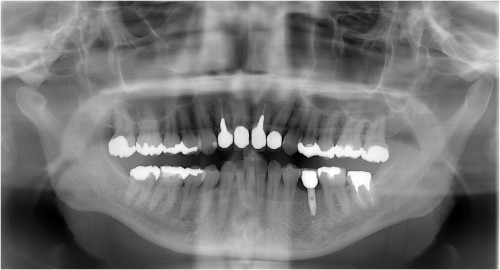

術前

抜歯後

埋入前(抜歯後約6ケ月)

上記、拡大写真

インプラント埋入直前

インプラント埋入時

同拡大

支台装着

被せ物装着

同全体写真